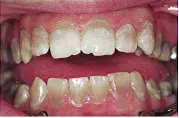

Dentinogenesis Imperfecta

این ناهنجاری اتوزومال غالب است و تکامل غیر طبیعی عاج شیری و دائمی را بدنبال دارد. دارای سه نوع 1 و 2 و 3 می باشد. هر سه نوع DI  توبول های عاجی نا به جا و در جهات نا مناسب تولید می کنند . دندان های شیری شدید تر از دندان های دائمی مبتلا می شوند به نحوی که آخرین دندانی که رویش می یابد از همه دندان ها درگیری خفیف تری بروز می دهد. دندان های یاد شده از لحاظ کلینیکی هنگام رویش ظاهر طبیعی دارند ولی در طول مدت کوتاهی تغییر رنگ یافته و به رنگ کهربایی تا خاکستری –قهوه ای یا شفاف دیده می شوند. مینا از روی این عاج ناقص به صورت لایه لایه کنده شده و باعث ایجاد شیارها و سایش قابل توجهی می شود.